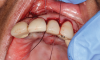

Following infiltration of the facial attached gingiva and palatal area with articaine hydrochloride 4% and epinephrine 1:100,000 (Septocaine®, Septodont [alternatively: Articadent®, Dentsply Sirona; Orabloc®, Pierrel]), an envelope releasing incision was made extending one full tooth over. To prevent trauma to the mucosal tissue, vertical incisions were not made (Figure 3). Incising the mucosa results in the release of prostaglandins and histamine, which increases postoperative discomfort. For this patient, staying in attached gingiva provided excellent control of the flap and allowed clear access to the apical lesion.

(3.) An envelope reflection was made with no vertical incisions, exposing the entire bony defect affecting the apical portion of the stable implant.

Figure 3